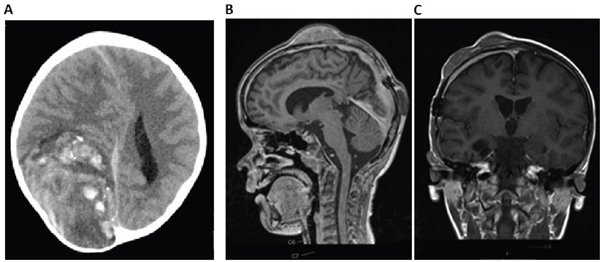

A 6 year old, male patient was transferred to our hospital due to a large (92 x 61 x 87 mm) hemorrhagic tumor in the right parieto-occipital lobe (Figure 1A). The tumor was macroscopically completely resected and the first local histopathological report was suggestive of a high grade malignant glioma (anaplastic astroblastoma with the differential diagnosis of glioblastoma). The reference pathology laboratory was also unable to come to a definite diagnosis and referred to it as a malignant, partly neuroepithelial tumor. The postoperative staging scans revealed no metastases. With a presumed diagnosis of a malignant glioma, we initiated treatment according to the HIT HGG protocol (cranial irradiation with 59.4 Gy in 30 fractions with concomitant oral temozolamide chemotherapy). Meanwhile, his FFPE tumor sample was analyzed by the Molecular Neuropathology 2.0 diagnostic pipeline and the 450k methylation array analysis revealed a “primitive neuroectodermal tumor with WNT-like subtype”. Due to these novel findings, we added 4 cycles of chemotherapy with vincristine, cisplatin and CCNU according to the HIT-Med protocol. After 4 cycles of chemotherapy the boy developed three inoculation metastases at his skullcap (Figure 1B-1C). Resection of the metastases was performed and the analysis of these samples revealed the same tumor entity. The patient is currently receiving radiotherapy of the three metastatic lesions as relapse therapy

Figure 1: Imaging of CNS HGNET-BCOR primary tumor and metastasis. A. cCT scan of the primary tumor reveals a 92 x 61 x 87 mm large tumor in the right parieto-occipital lobe. B-C. cMRI shows three inoculation metastases on the skullcap.